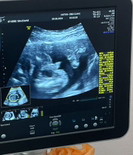

เพศลูก แอบหวังชาย แต่คงไม่หด กลับไปเป็นหญิงนะคะ หมอแจ้งแค่อาจจะ แต่ยังไม่ชัวร์ค่ะ

16วีค แบบนี้ชายหรือหญิงคะแม่ๆ

ชาย100%ค่ะแม่ไม่มีหดแล้ว

บ้านนี้ลูกชายชัดแจ๋วเลยค่ะ

ของเค้าโผล่แบบนี้ ผช ค่ะ

น่าจะชายแล้วนะคะแบบนี้

ชายแน่นอนค่ะแม่